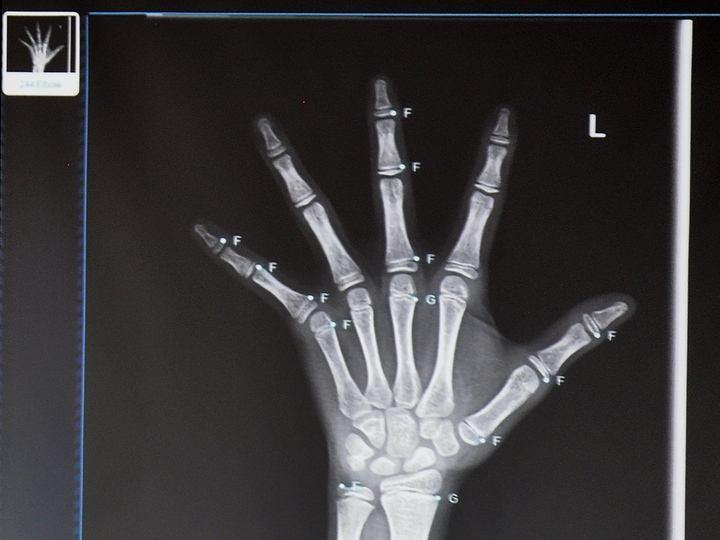

手掌骨骺线闭合区别图 第1页

骨骺线是骨骺与干骺端之间的软骨,它在x光片上表现为一条较宽的透光带